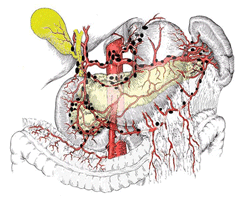

Согласно Основным правилам, регионарные лимфатические узлы желудка (см. рис. 5 на цветной вклейке) разделяются на 3 этапа регионарного метастазирования. Такое разделение основано на прогностической значимости поражения различных групп лимфатических узлов в зависимости от локализации первичной опухоли в желудке. Наиболее часто ;к лимфатическим узлам первого этапа метастазирования относятся перигастральные лимфатические узлы, расположенные в поверхностных связках желудка. В зависимости от локализации эти лимфатические узлы разделяются на 6 групп:

Рисунок 5. Лимфоузлы желудка перигастральные, по ходу чревного ствола и его ветвей